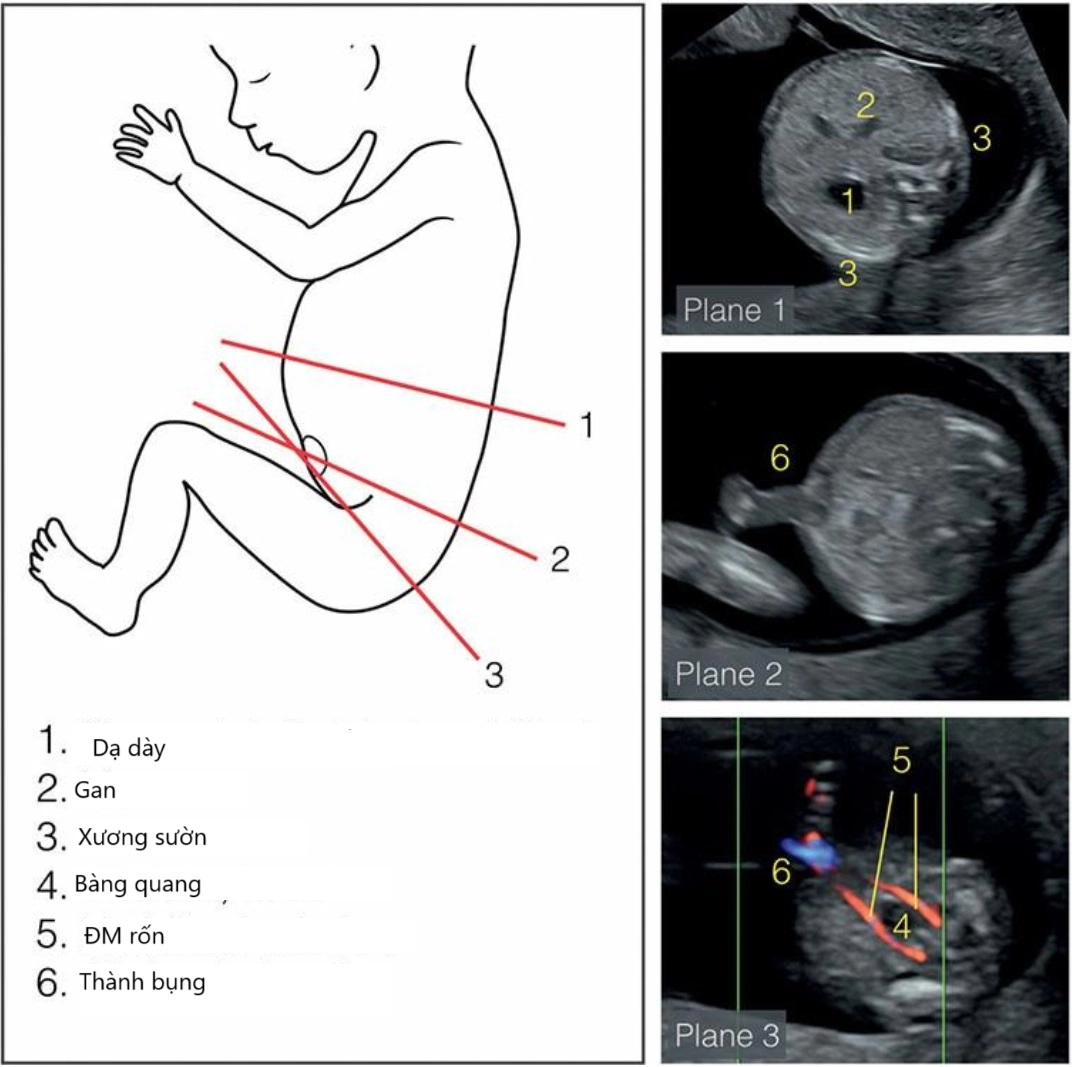

• Giải phẫu siêu âm đường tiêu hóa thai quý I

• Giải phẫu siêu âm mạch máu bụng thai quý I